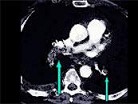

- 多项选择题该病人突发胸部疼痛,进行性呼吸困难, 行X线片检查,提示右下肺病变, 急诊CT平扫加增强,如图所示 ( )

A、X线片示右下肺实变影

B、SCT增强扫描示右侧肺动脉主干完全性充盈缺损

C、右肺动脉开口处见不规则软组织密度影

D、考虑为右侧肺动脉(中央性)栓塞